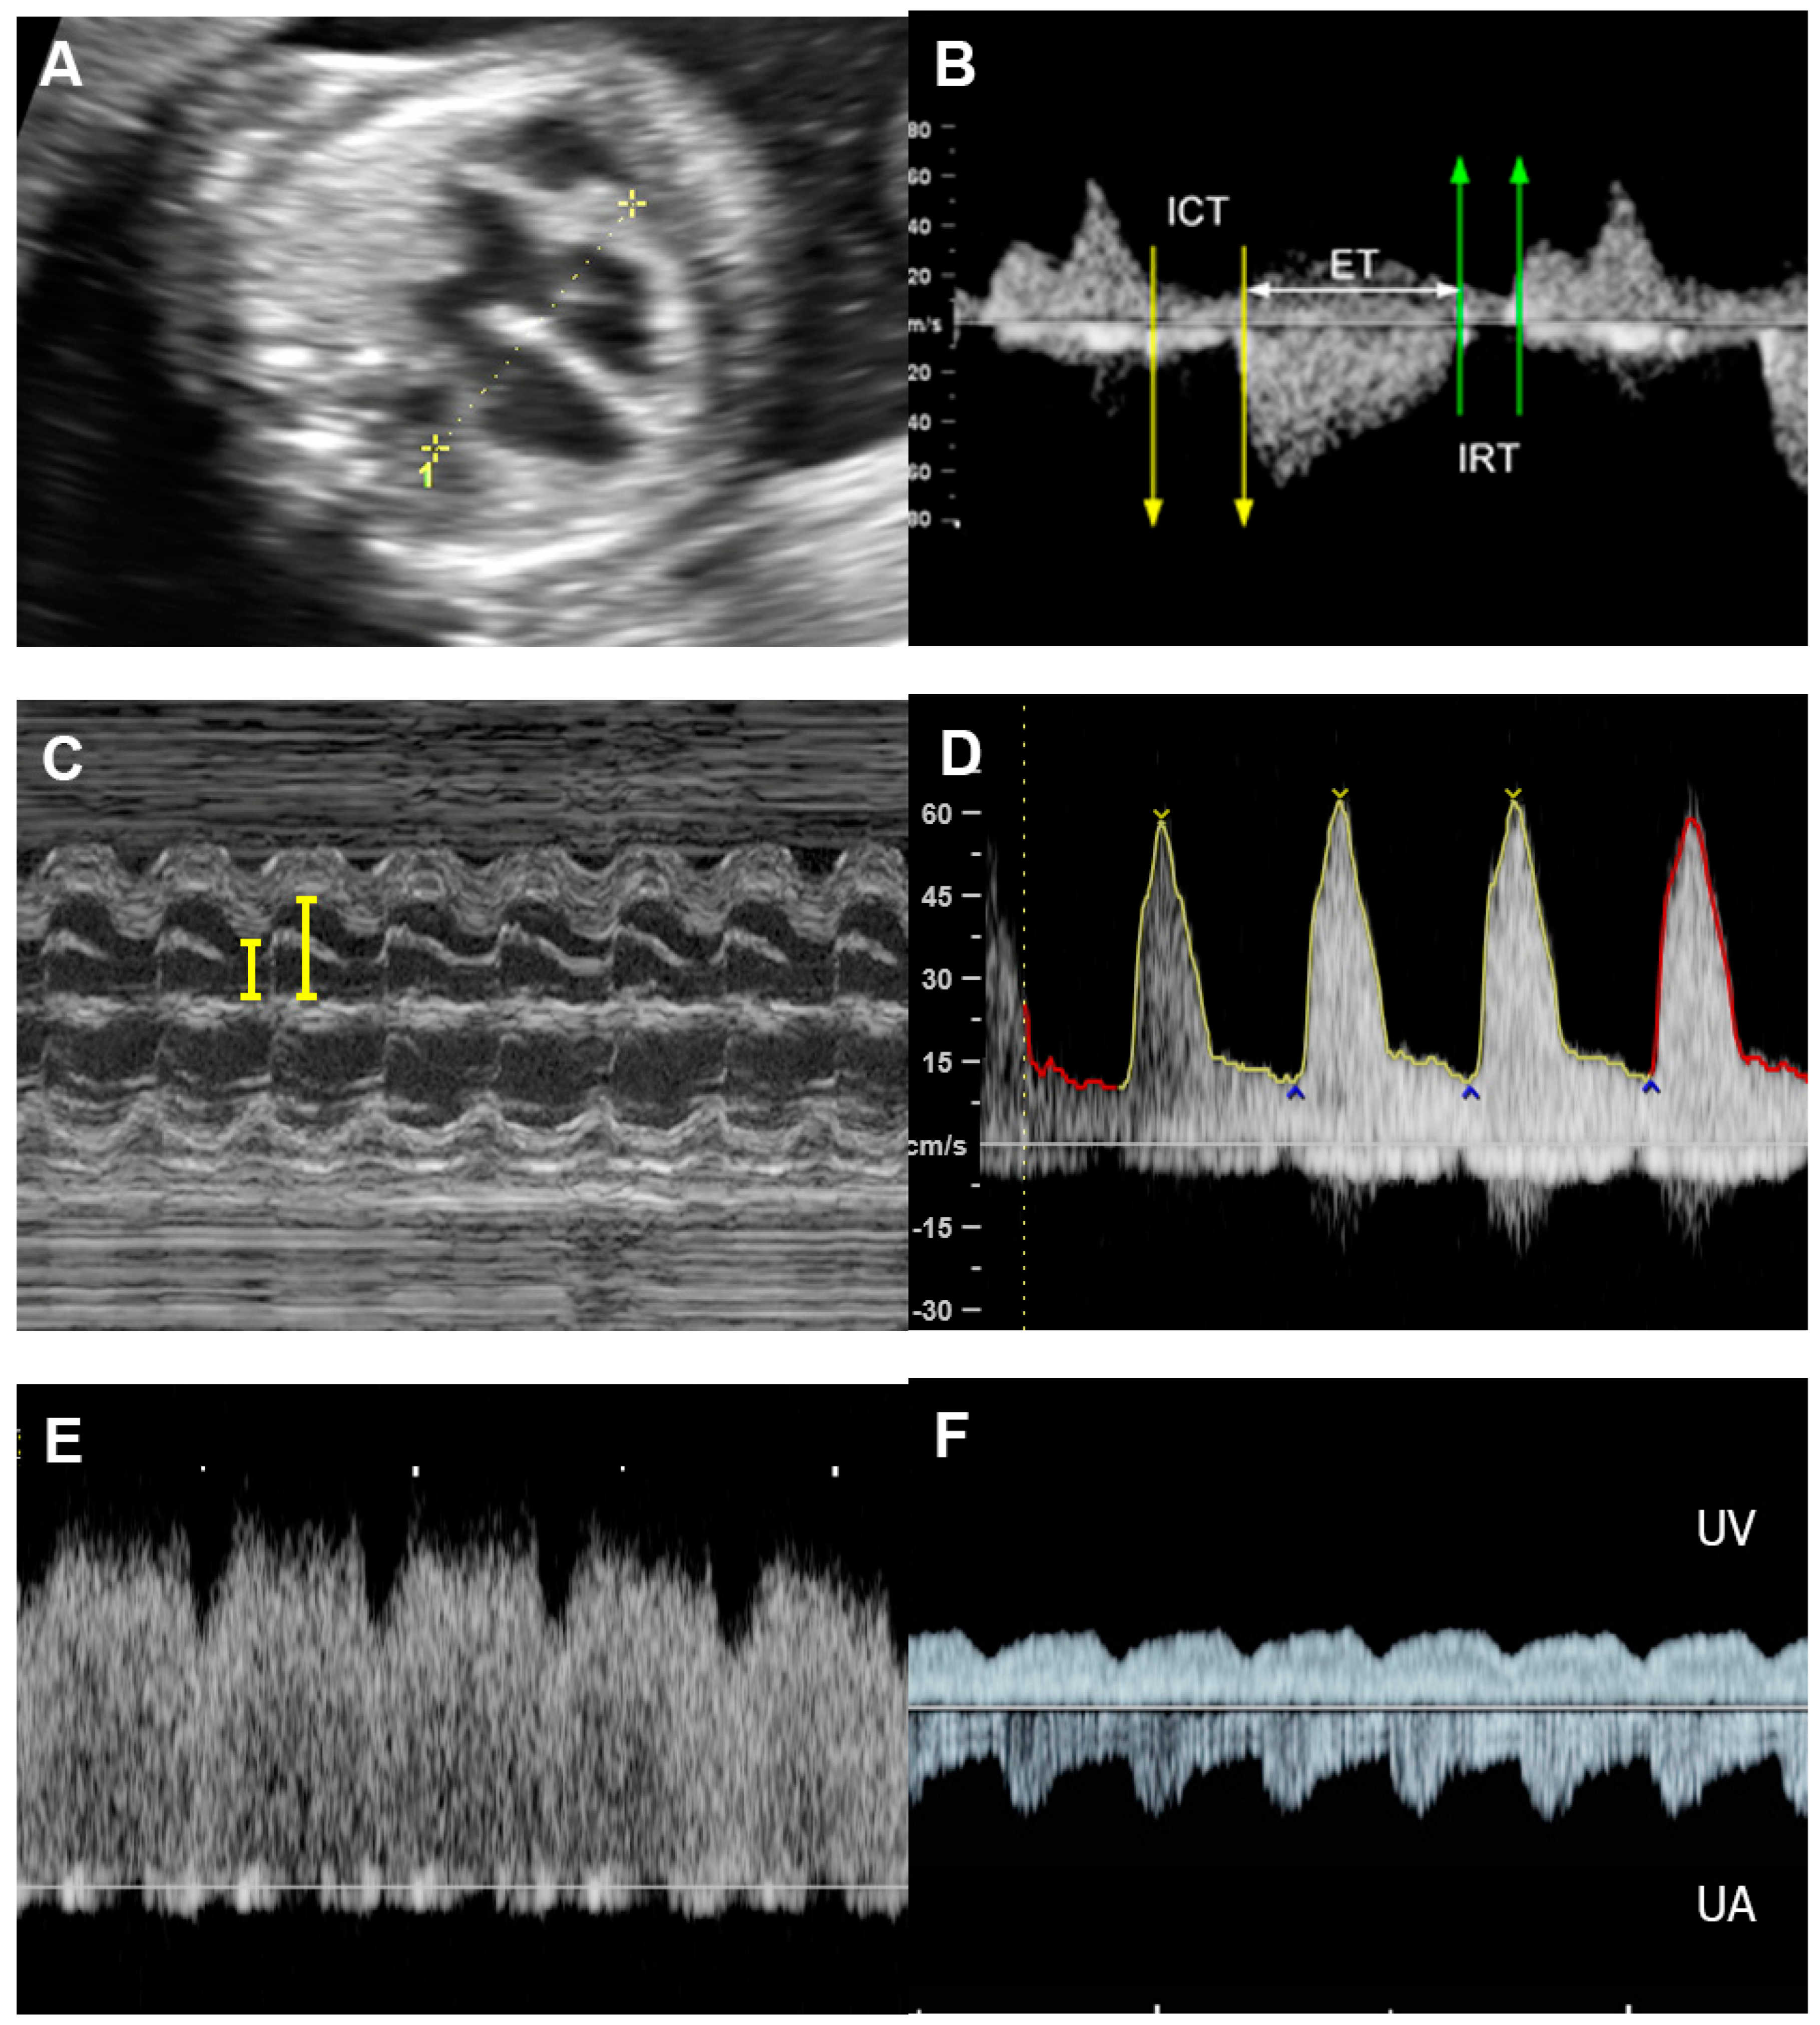

4.5. The Myocardial Performance Index (MPI)

4.6. Ventricular Inflow

4.7. Systemic Venous Pressure